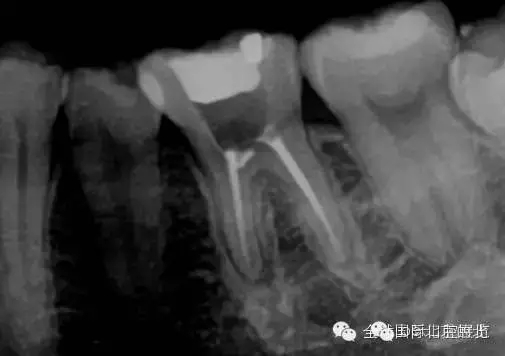

是遺漏了,但是又有新的問題出現(xiàn),無法找到根管口,我一般會(huì)用8#Kfile去尋找根管,CBCT上看就在眼前,但是我就是看不到,也無法進(jìn)入,此時(shí)操作也快一個(gè)小時(shí)了,患者也覺得累了,所以MB暫且停止尋找,因?yàn)橐泊_實(shí)無法進(jìn)入,所以把ML,MM根充完成,準(zhǔn)確測(cè)量長(zhǎng)度,AH-Plus,根管糊劑,涂布根管壁,冷牙膠依次充填完成暫封,下周繼續(xù)尋找失落的根管,同時(shí)也要把頰側(cè)楔缺的位置封閉好,防止再感染,再?zèng)]有橡皮障的保護(hù)下盡量減少感染機(jī)率。

終于找到MB了,然后把根管口MM,ML封閉,S3機(jī)擴(kuò),F(xiàn)1.04錐度牙膠試尖,期盼了好久的柳暗花明終于出現(xiàn)。

終于完成根充

MM,ML其實(shí)融合為一個(gè)根管口的,截面就是三根管的形態(tài),然后做了一個(gè)簡(jiǎn)單清晰的三維重建,形態(tài)還是挺不錯(cuò)的 。